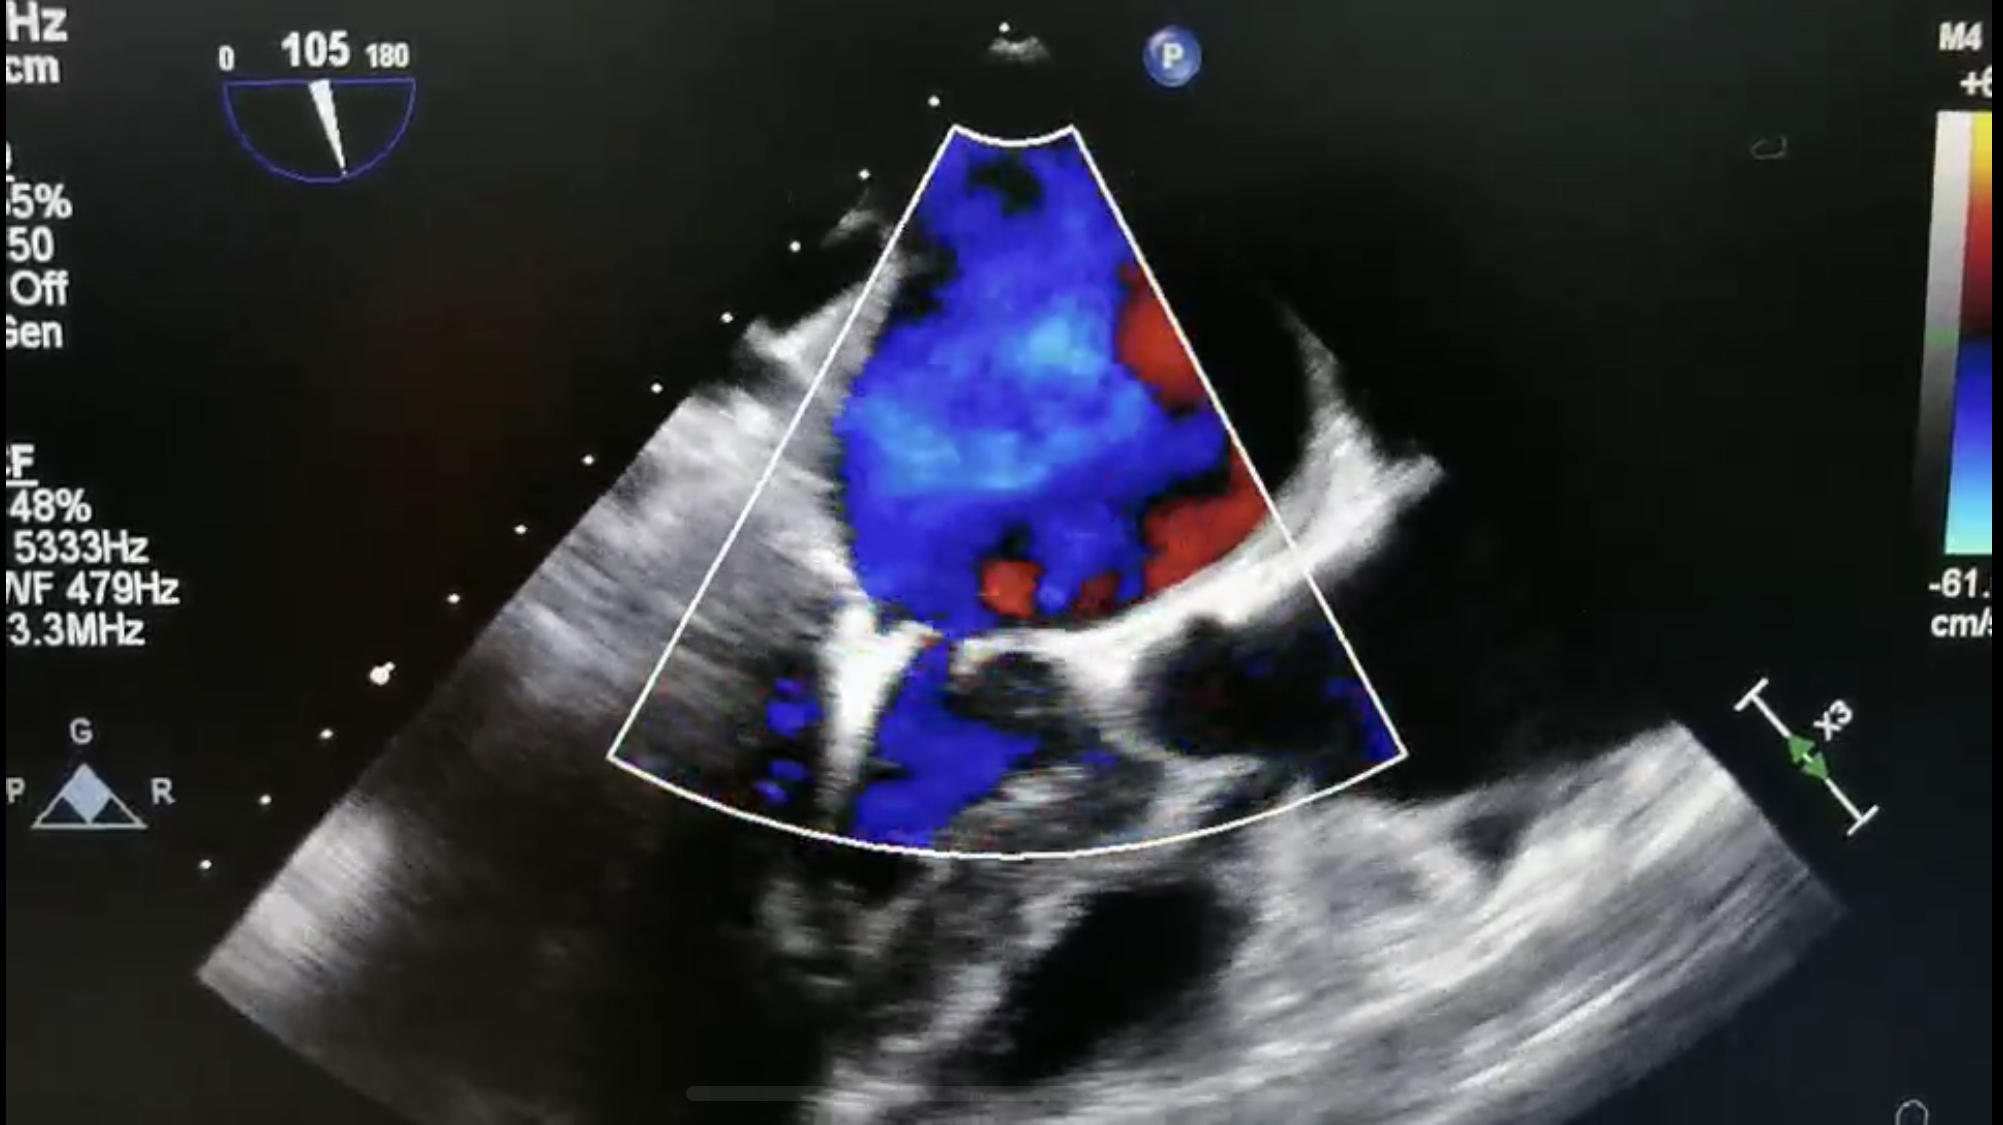

患者术前及术后彩超

释放二尖瓣夹后,超声显示返流程度由大量转为少量返流,患者各项生理指标正常,手术顺利完成,耗时约两小时。